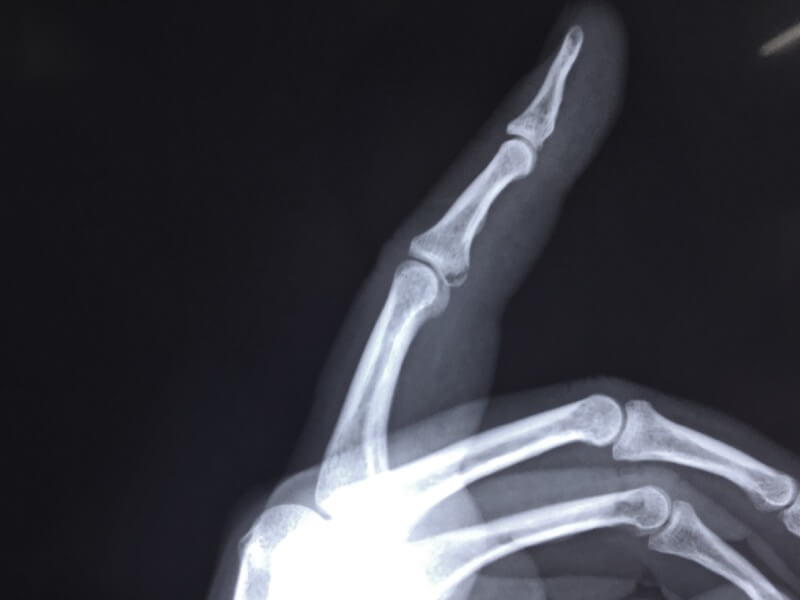

人生初の骨折。軽症のようですが、全治1ヶ月とか。信じられません(T_T)